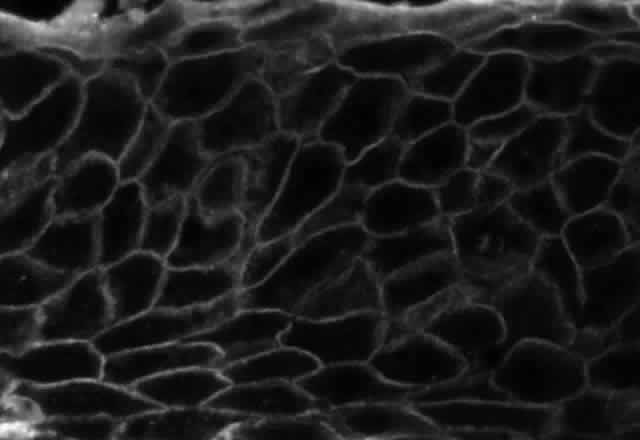

Pemphigus can be differentiated from bullous pemphigoid and from cicatricial pemphigoid on histologic and immunologic bases. Whereas the bullae in pemphigus are intraepidermal, those occurring in bullous pemphigoid and in cicatricial pemphigoid are subepidermal, between epidermis and dermis, or between mucosa and submucosa. Acantholysis is not present in the latter two conditions.5 In bullous pemphigoid and in cicatricial pemphigoid there are tissue-fixed immunoglobulins in the subepidermal basement membrane zone (Fig. 2).11 This is in contrast to the interepidermal fixation of antibodies (Fig. 3) seen in pemphigus (Table 1).

Fig. 3. Immunofluorescence microscopy of conjunctiva from a patient with pemphigus vulgaris. The antibody is a fluorescein-conjugated antibody directed against human IgG. Note the bright staining of the intercellular cement, brightly outlining the borders of all of the epithelial cells.